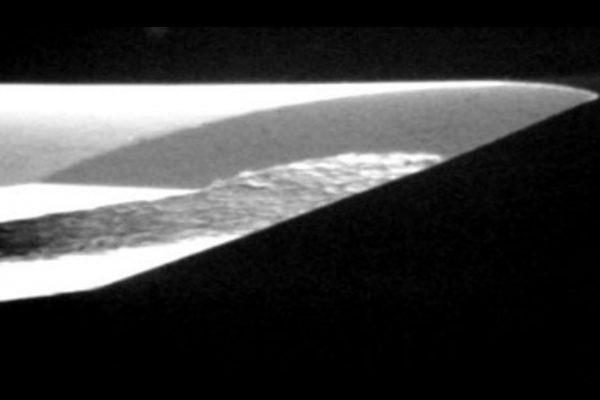

A clinical case of a necrotic UR6 associated with periapical periodontitis

Curved and sclerosed canals can raise difficulties for the operator during root canal treatment resulting in iatrogenic errors. In this…